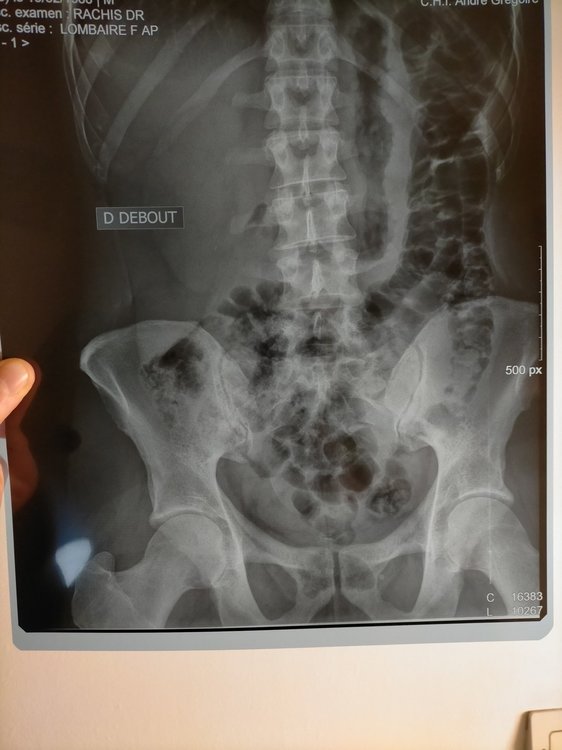

Bonjour à tous, Tout d'abord bravo pour ce forum et pour le travail de M. Blondeau. J'ai parcouru de nombreux sujets et appris beaucoup de choses. Je me permets un nouveau sujet, étant un peu perdu dans mes démarches et mon positionnement. Je pratique le vélo depuis 6 mois, de manière plutôt assidue, environ 1000km par mois (home trainer en semaine et sorties de 150km en moyenne le weekend).Depuis le confinement, 100% home trainer. Mon objectif 2021 est l'ultra distance type bikingman et de longs voyages à vélo pendant les vacances, en autonomie (vélo chargé). J'ai développé un syndrome rotulien aux deux genoux (dont droit +++) à la fin de l'été 2020, à cause d'une selle réglée trop bas, d'une mauvaise technique de pédalage et d'un trop grand nombre de kilomètres (j'ai largement grillé les étapes). Résultat : trois semaines d'arrêt, médecin du sport, IRM/Radio, infiltrations genou droit et étude posturale. J'ai repris progressivement depuis l'étude posturale mais j'ai développé de nouvelles douleurs : arrière des genoux (ça tire pendant effort et douleurs les jours qui suivent) + tendons d'achille (si je force trop ou roule trop de km/D+, j'ai des inflammations le lendemain et/ou douleurs). J'ai aussi la sensation d'avoir la jambe droite plus courte, de devoir forcer et d'avoir moins de puissance/contrôle quand je pédale rond. Mon ostéo a remarqué une différence de 2/3 mm entre ma jambe droite et gauche. Je pense que ma selle est trop haute . Le physio qui a réalisé mon étude postale m'a invité à baisser ma selle d'1 cm mais les douleurs sont encore là. Je ne veux pas baisser trop par peur de réveiller les problèmes initiaux (syndromes rotuliens). Je fais depuis ma reprise du gainage, des étirements, du yoga, du renforcement quotidien et je fais attention à ma récup et la progressivité de la charge de travail mais on est encore loin de la perfection physiquement et j'ai toujours des douleurs. MA QUESTION : en me filmant sur mon home trainer, j'ai remarqué une franche bascule du bassin vers la droite. J'aimerais ajouter une rehausse cale de 5mm pour compenser et rendre mon réglage de hauteur de selle moins compliqué. Certains disent que c'est une bonne idée (exemple), d'autres que non. Que me conseillez vous ? Voici une videos de dos sur home trainer avec selle à 73,8cm (pas de douleur derrière les genoux ni aux talons d'achille. Sensation de confort global mais tension dans les genoux/rotules). En dessous une video 10 jours plus tot, de profil, avec elle à 75cm (gene derrière les genoux et talons d'achille) Mesures étude posturale : Membre supérieur : Acromion - styloide cubitale : 55cm Tronc : Grand trochanter - Milieu Acromion : 57cm Femur : grand trochanter - condyle externe genou = 43cm à gauche et 43 cm à droite Jambe : condyle externe genou - Malléole externe cheville = 43cm à gauche et 43 cm à droite Entre-jambe : 85cm (mais je trouve entre 83 et 84 en mesurant moi même) Flexibilité : bof bof mais j'y travaille. Cotes étude posturale : Hauteur cadre et longueur du cadre : 54 (OK) Inclinaison : 155mm Axe de pédalier - Apex de selle : 76 cm (douleurs depuis) Fond de selle - axe de guidon : 79 cm (OK) Sortie de potence : 30 mm (OK) Longueur potence : 100 mm (OK) Longueur manivelle : 170mm (OK) Largeur guidon conseillée : 42cm (OK) Cales chaussure : Look keo rouge (OK) avec conseil de réglage suivant : "tout à fond vers le haut de la chaussure". J'ai ajouté une rehausse cale de 1mm à droite depuis que mon osteo a constaté le différence de hauteur de jambe Quelques images récentes : Radio bassin juillet 2020 (suite accident) : en PJ Compte rendu radio : rectitude rachidienne lombaire dans le plan sagittal, respect de hauteur des corps vertébraux, pas de recul mur posterieur, discret pincement L4-L5 et L5-S1 Radio des genoux suite syndrome rotulien : RAS IRM genou droit : petite ulcération du cartillage patellaire medial associé à une enthésopathie à minima d'insertion rotulienne du ligament patellaire sans patella alta ni signe de dysplasie femoro-patellaire.